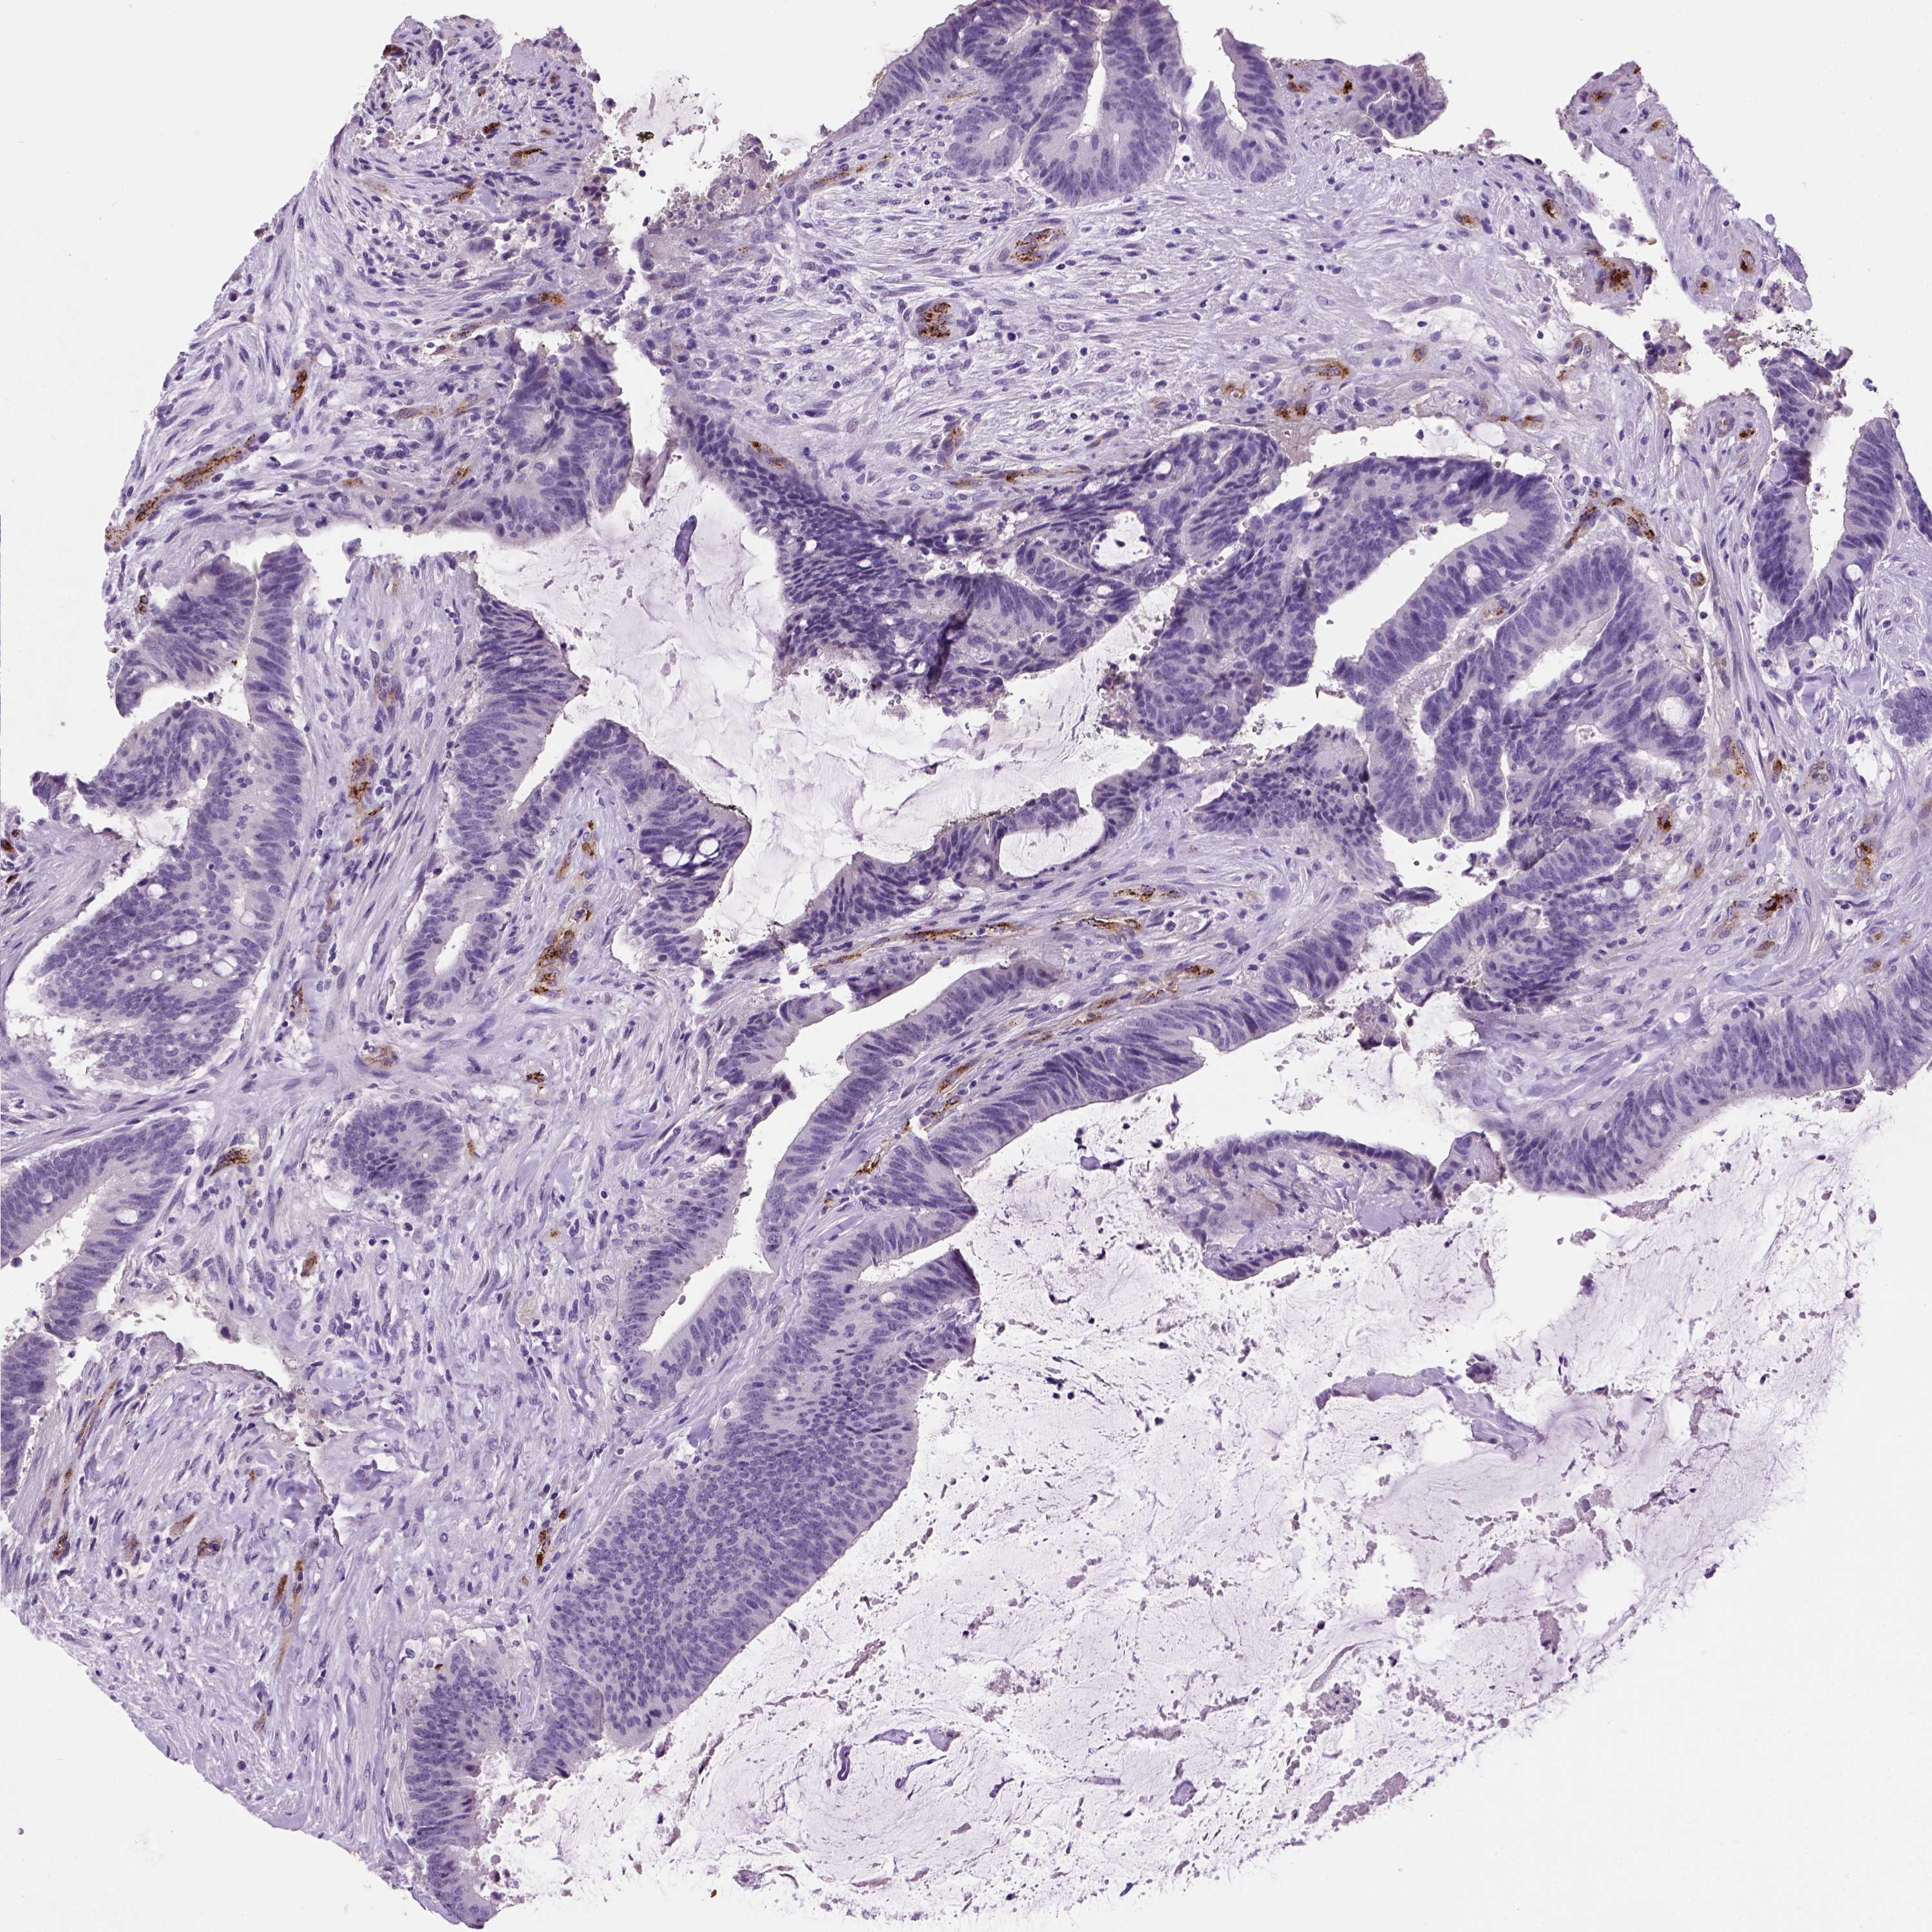

CANCER COLORECTAL CANCER Show tissue menu

COAD TCGA COAD VALIDATION READ TCGA READ VALIDATION PROTEIN COAD CPTAC PROTEIN EXPRESSION

ANTIBODIES

AND

VALIDATION